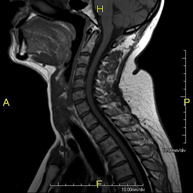

- RM Columna cervical

Prueba diagnóstica no invasiva que consiste en la obtención de imágenes de alta definición anatómica de la columna cervical mediante el empleo de un campo electromagnético y ondas de radio (con un emisor y un receptor). No utiliza radiación ionizante. Indicaciones: traumatismo, degeneración de la columna, hernias. - RM Columna dorsal